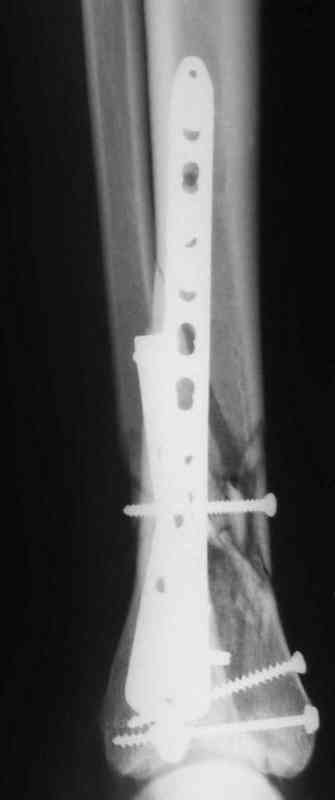

В настоящее время больной в реанимации по поводу Черепно Мозговой Травмы и состояние улучшается. Запланировал ушивание раны в пятницу, если позволит состояние мягких тканей и при отсутстви отека возможно удастся просунуть перкутанномедиальную пластину.

КТ пилона имеем.